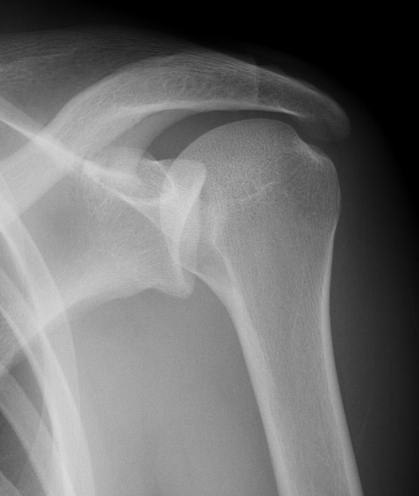

Scapular lateral

Center of the humeral head must be centered on the Y / Mercedes sign

Y is formed by

- coracoid anteriorly

- scapular spine posteriorly

- scapula body inferiorly

Normal scapular lateral

Posterior shoulder dislocation